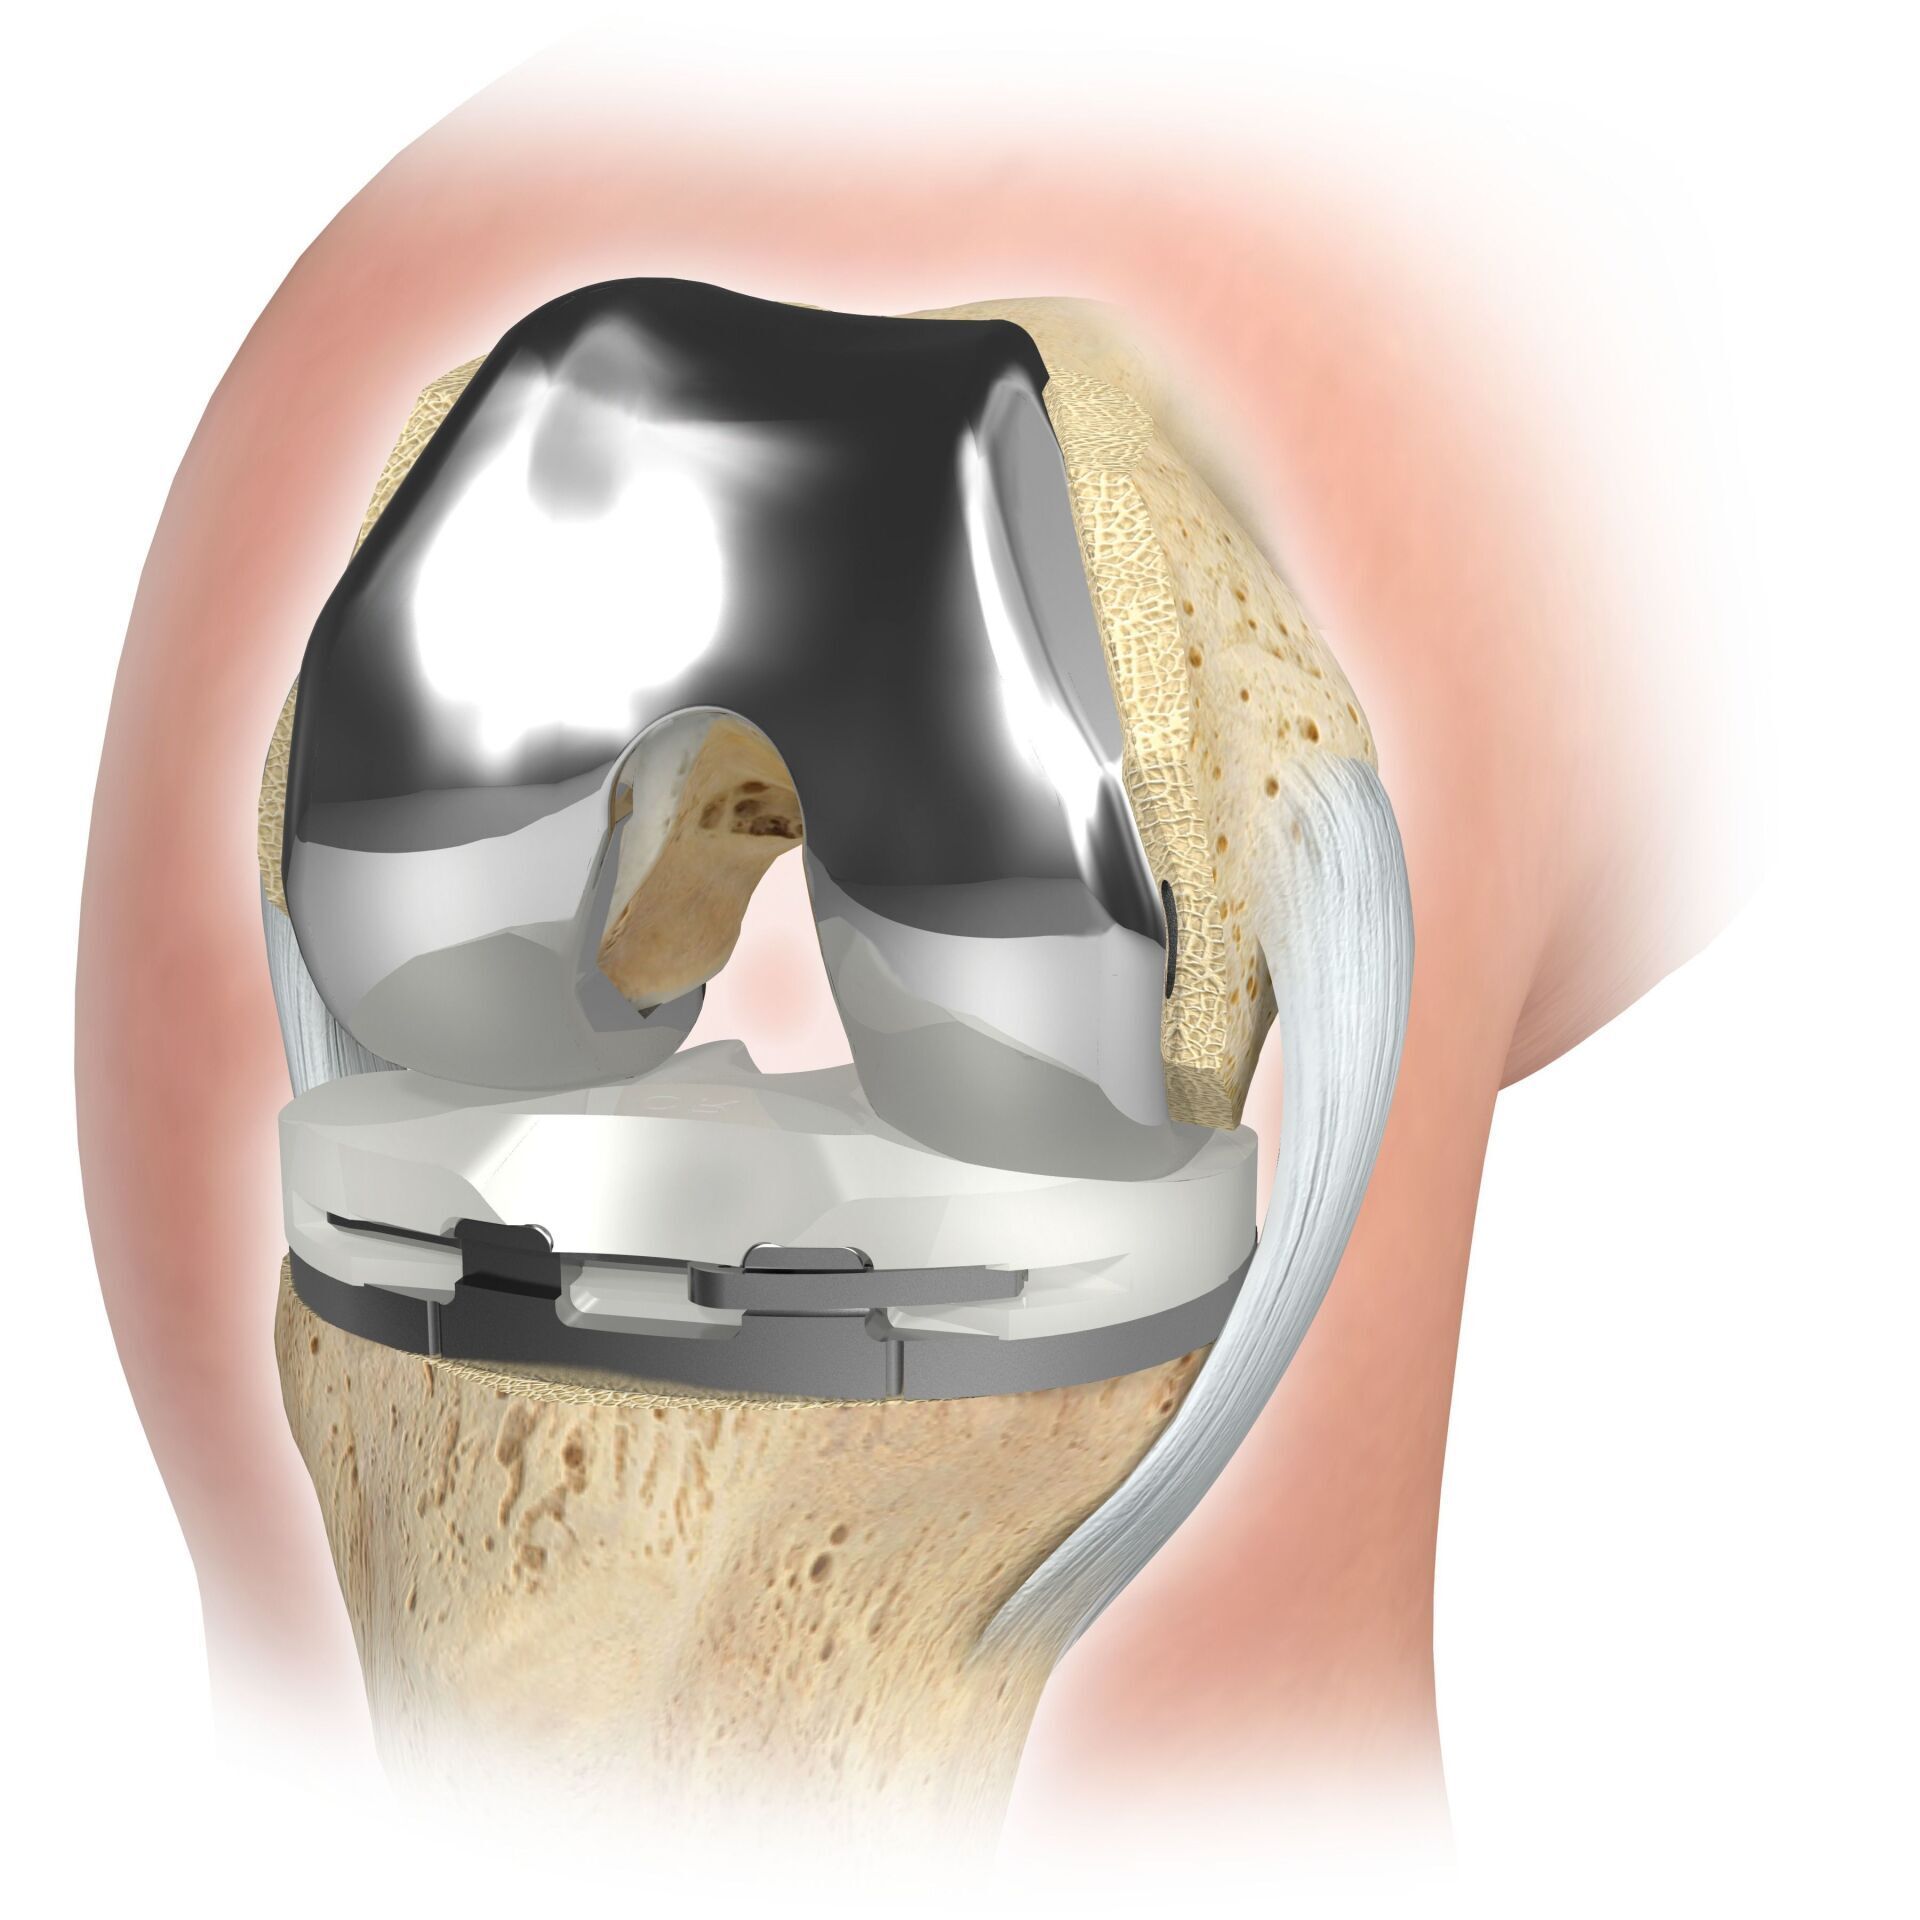

L’articulation artificielle du genou remplace la surface cartilagineuse détruite par l’arthrose. L'os sous-jacent du fémur et de la tête tibiale reste intact. Certains comparent une articulation artificielle moderne du genou à un couronnement de dent ; le terme exact est ce qu'on appelle le resurfaçage bicondylien. Entre les nouvelles surfaces sur la partie supérieure et inférieure de la jambe se trouve ce que l'on appelle une incrustation en plastique blanc spécialement durci, qui peut être vue sur l'image radiographique comme la distance entre les pièces métalliques.